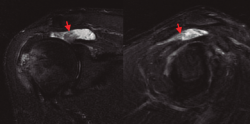

Figura 2. Imágenes en corte sagital y axial de las ventanas T1, T2 y supresión grasa de la RM, evidenciando una masa vellosa en el receso suprapatelar con intensidad de señal grasa, (señaladas mediante flechas), asociada a un derrame articular.

En la resonancia magnética (RM) de los hombros, los citados cambios degenerativos con ­quistes subcondrales en la cabeza humeral y presencia de cambios inflamatorios en cabeza y troquíter eran evidentes, observándose el LA como una infiltración grasa con vellosidades en la cavidad articular hiperintensas en T1 y T2, con imágenes hipointensas en las ventanas STIR y supresión grasa. También se observó el acúmulo de líquido en la zona de la bursa subacromial (Figura 1), presentando en ocasiones una discreta migración proximal de la cabeza humeral. En ocasiones se evidenció también una alteración de la señal en los tendones del manguito rotador, compatibles en algún caso con roturas. En la RM de los casos de rodilla se evidenció el LA como un crecimiento de partes blandas en la bursa suprapatelar de intensidad compatible con la grasa, asociada a la presencia de derrame articular (Figura 2). Dicha masa era heterogénea, irregular, adherida al plano anterior.